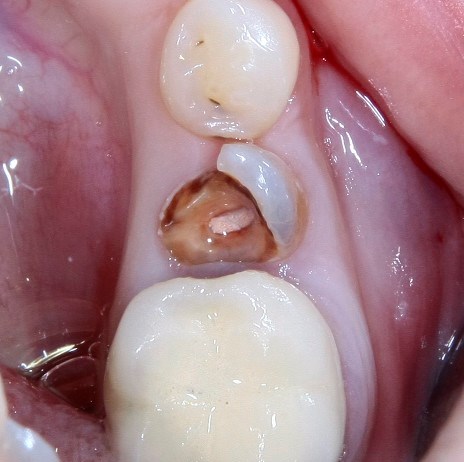

Немедленная имплантация — оптимальное решение в любой клинической ситуации